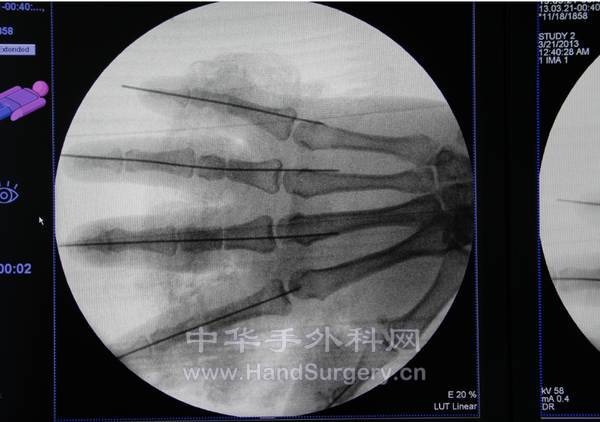

前天值班来了一个5指离断的病人,除了拇指吻合了2动2静,其余手指均吻合了2动3静,手术很累.但手术费呢,第一个断指1880元,第2-5个每个800元,总共收了1880+800X4=5080,这就是吻合了24条血管10条神经6根肌腱的费用。还不如残修每个900元来的多。呵呵,收费严重不合理。罢了,权当做了善事。

术前:

QQ截图20130322002417.png

QQ截图20130322002449.png QQ截图20130322002435.png

术后:

QQ截图20130322002505.png QQ截图20130322002524.png